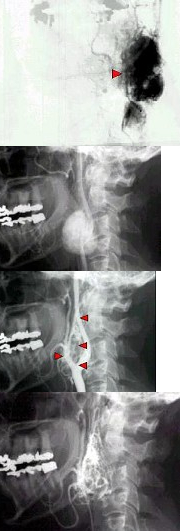

133、单项选择题

男,71岁,背部酸痛,低热,乏力,消瘦2月余,结合影像学表现,最可能的诊断是()

A.脊柱转移瘤

B.化脓性脊柱炎

C.脊椎结核

D.椎体压缩骨折

E.阻滞椎